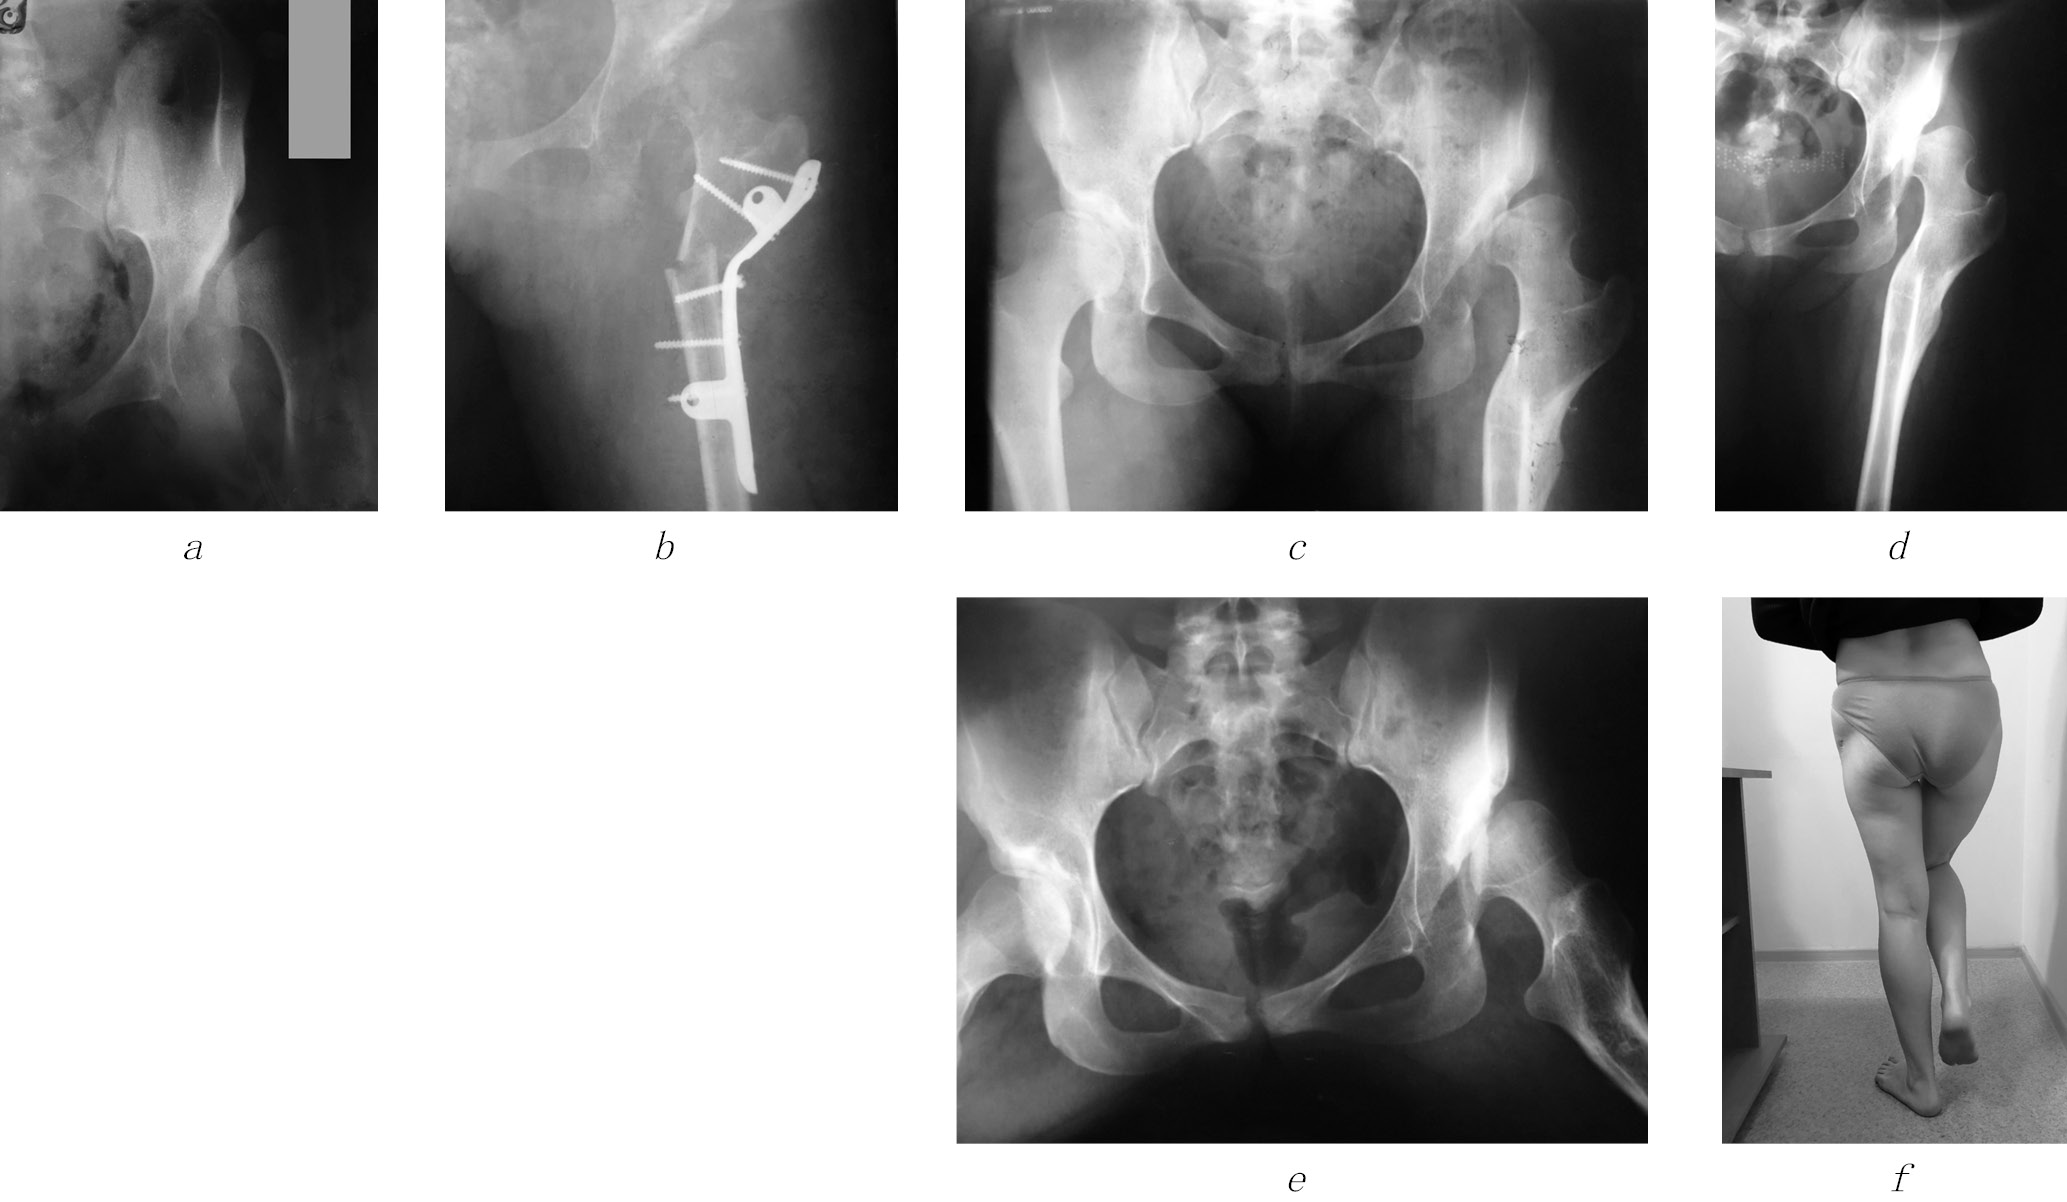

At the age of 15 years, the patient was admitted with complaints of pain in the hip joint on the left, lameness, shortening of the limb by 4 cm. The radiograph revealed a dislocation of the left hip with moderate neoarthrosis in the peri-acetabular region, subchondral sclerosis (Fig. 5, a). After the examination, taking into account the X-ray image, the patient’s age and clinical data, in 2004 a surgical intervention was performed according to the technique we proposed (Fig. 5, b). The postoperative period was uneventful. The wound healed by primary intention. After a week, rehabilitation treatment was started, the patient was trained in rehabilitation treatment and was discharged home after 14 days with the use of a “derotational boot” for 2 months.

Fig. 5. Radiographs of patient D. with congenital dislocation of the hip on the left: а — before surgery (2004); b — after the surgery (2004); c — one year after removal of the surgical hardware; d, e — 15 years after the surgery (2018); f — Trendelenburg symptom 15 years after the surgery

A year later, the hardware was removed (Fig. 5, c) and rehabilitation treatment continued. A follow-up examination was performed 15 years after surgery (2018); there were no complaints — the patient walked with a full load on the limb, without additional support, with a slight limp on the left lower limb. Functional shortening of the left lower limb by 1.5 cm is noted. The radiograph of the left lower limb reveals a restored biomechanical axis of the limb. The proximal end of the hip is valgized, the collum-diaphyseal angle is 145°, and the support points for the pelvis have been formed in the region of the lower edge of the acetabulum and a small trochanter (Fig. 5, d, e). The patient is married, has two children, is employed, and she is satisfied with the result of the surgery. The Trendelenburg symptom is not prominent (Fig. 5, f). Periodically, in the summer, she undergoes independent rehabilitation treatment in the territory of the North Caucasus. With a prolonged load on the limb, a minor pain syndrome is noted, which decreases with intake of non-steroidal anti-inflammatory drugs. The patient is not yet ready for hip joint replacement.